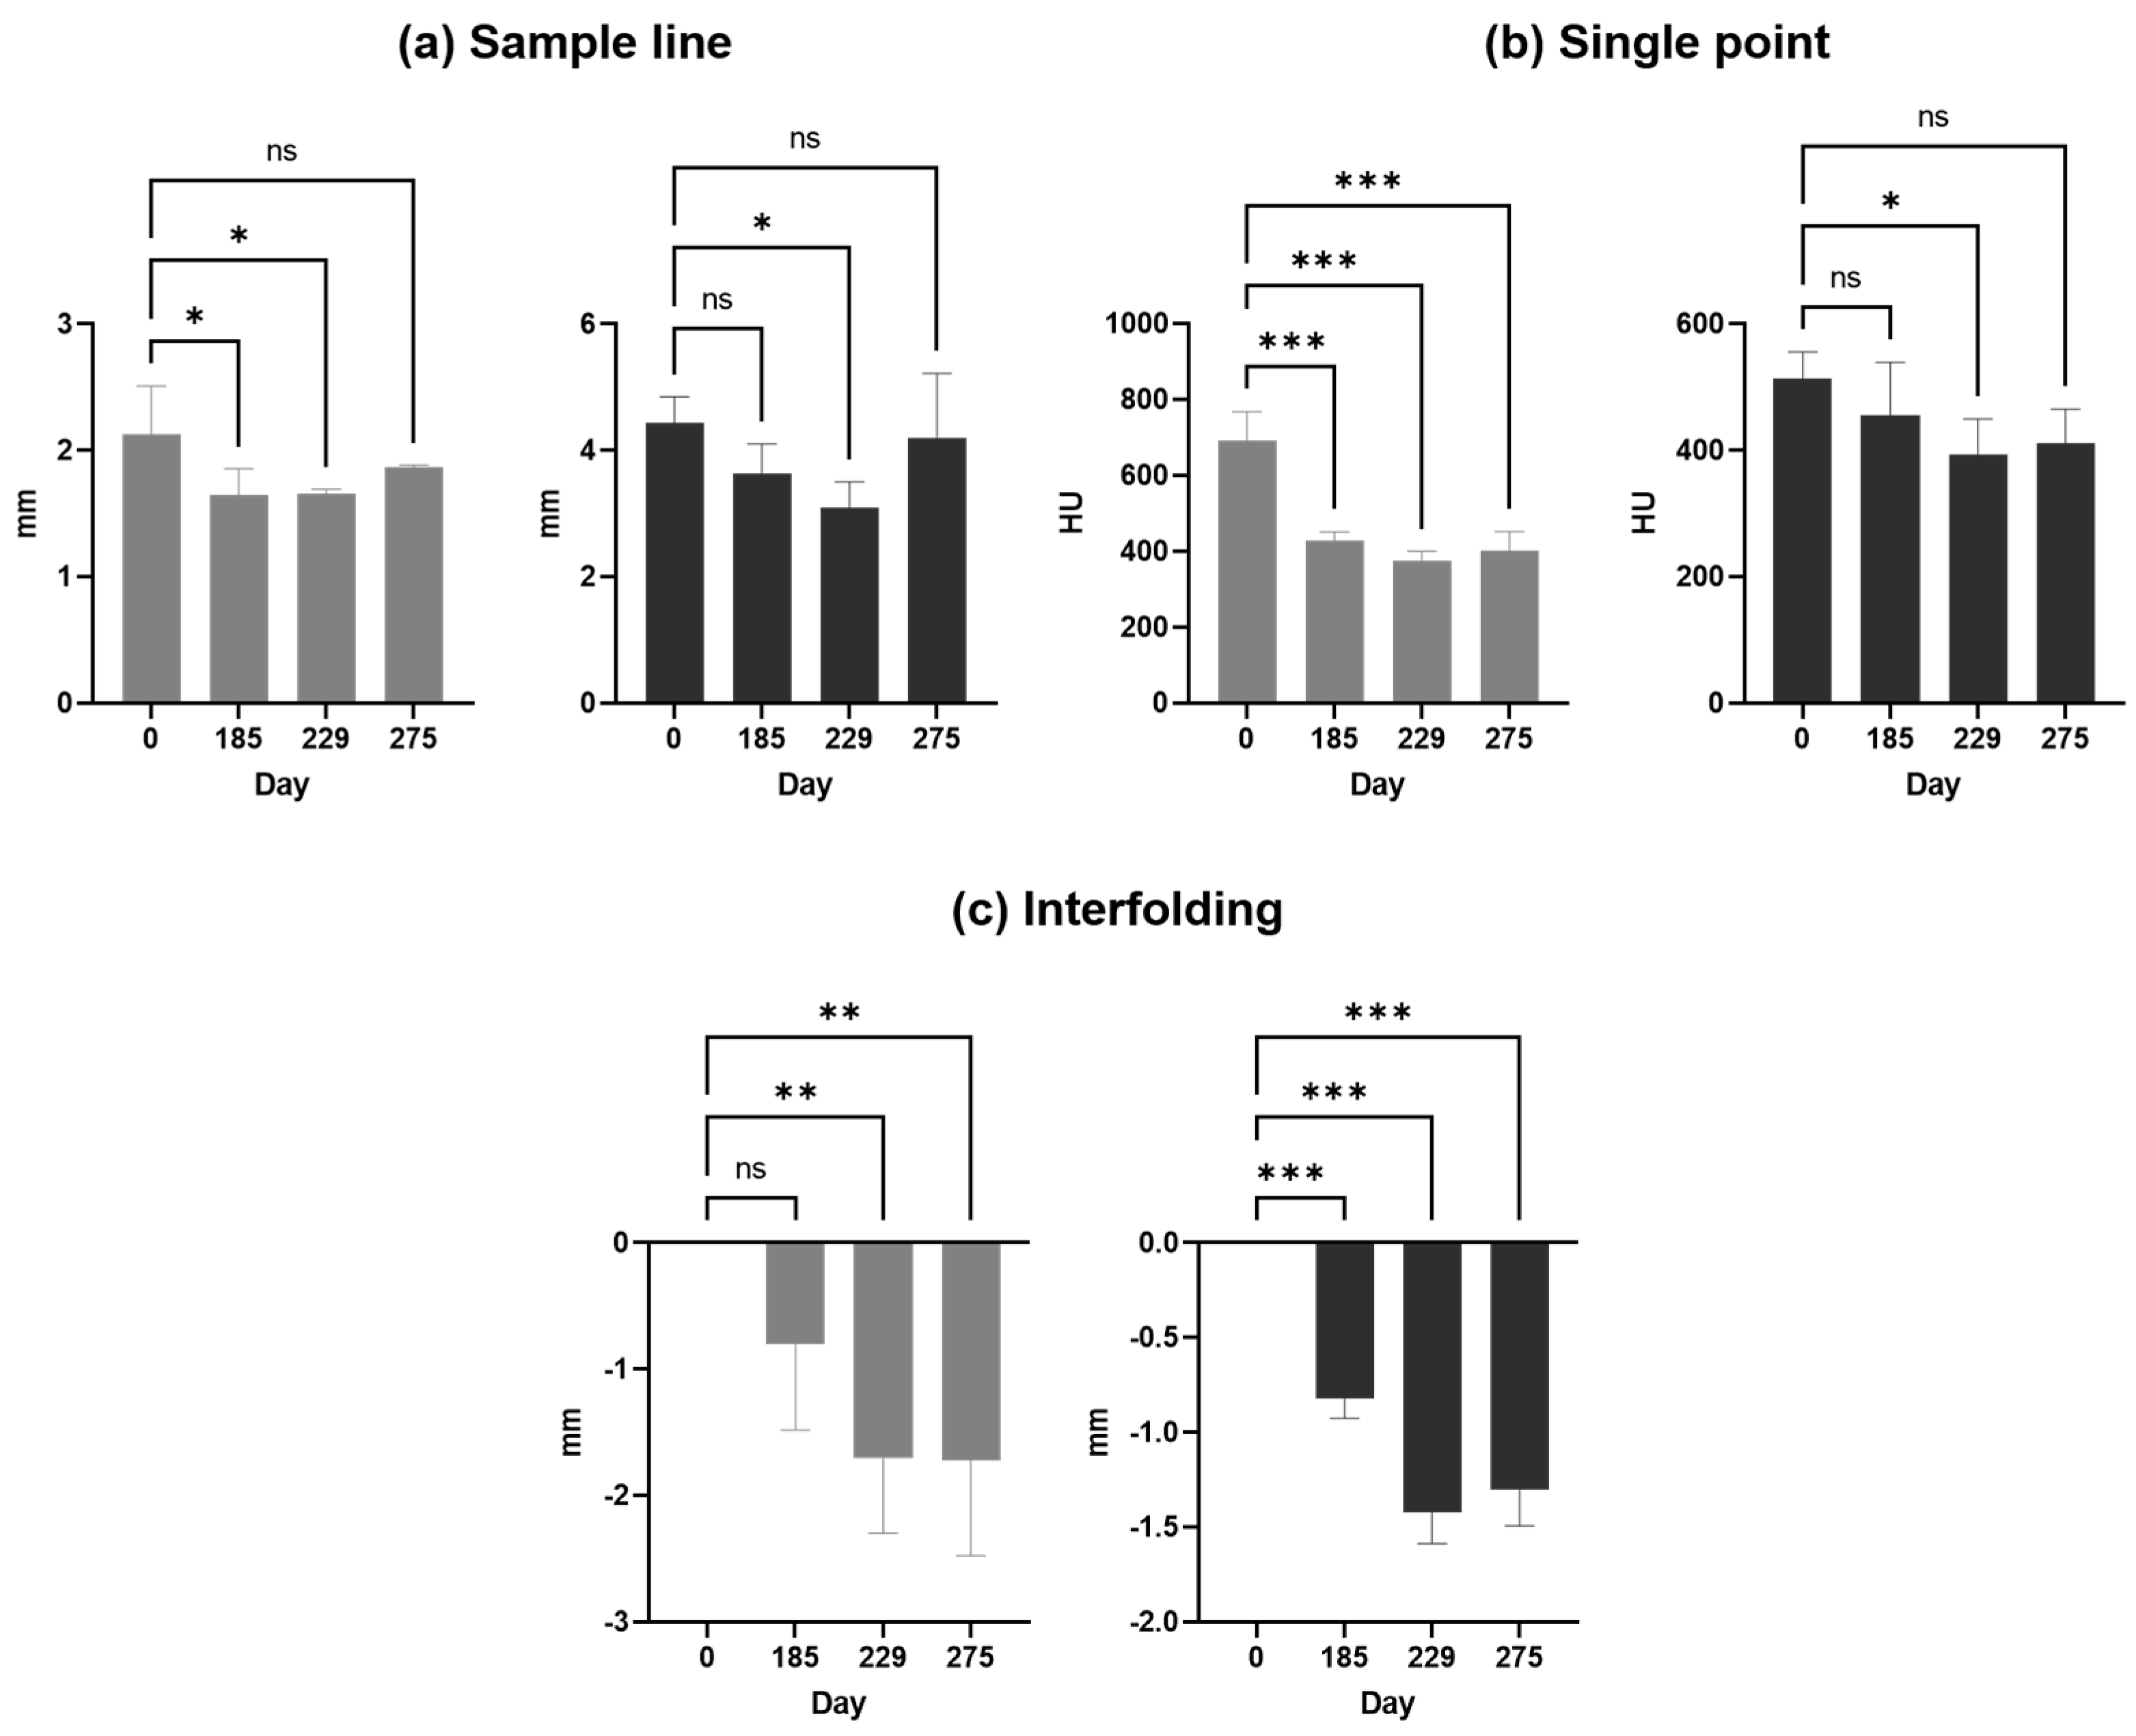

3.5. Comparisons of Changes in Bone Loss over Time

| p-Values Based on One-Way ANOVA | ||||||

|---|---|---|---|---|---|---|

| Hemisphere | Name | Units | 0 vs. 185 | 0 vs. 229 | 0 vs. 275 | 229 vs. 275 |

| Right | Single line | mm | 0.1559 ns | 0.0300 * | 0.6581 ns | 0.0614 ns |

| Single point | HU | 0.2840 ns | 0,0420 * | 0,0755 ns | 0.7166 ns | |

| Interfolding | mm | <0.0001 *** | <0.0001 *** | <0.0001 *** | 0.3148ns | |

| Left | Single line | mm | 0.0263 * | 0.0287 * | 0.1747 ns | 0.2745 ns |

| Single point | HU | 0.0001 *** | <0.0001 *** | <0.0001 *** | 0.4904 ns | |

| Interfolding | mm | 0.1356 ns | 0.0075 *** | 0.0072 *** | 0.9786 ns | |